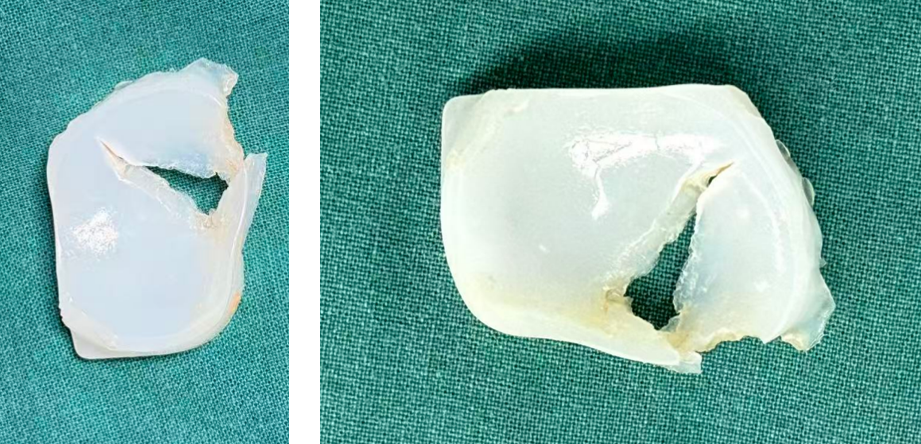

病例2:Bearing 破裂

病例2:Bearing 破裂的处理